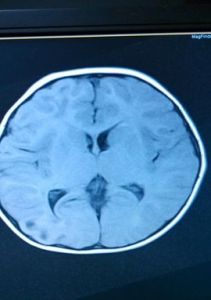

weber綜合徵一側中腦大腦腳腳底損害可出現大腦腳綜合徵(Weber syndrome),損傷動眼神經和錐體束,又稱動眼神經交叉癱,是指中腦腹側部,即大腦腳內側出現病灶,損害了同側動眼神經與位於腳底中部3/5的錐體束,而出現的動眼神經麻痹與偏癱同時存在的一種特殊症候群。

中腦腹側部綜合徵的病變位於大腦腳腳底,損害錐體束與動眼神經,因此發生同側動眼神經麻痹(眼瞼下垂,眼球外展位,眼球向上、內收及向下運動麻痹,瞳孔散大,對光反射消失)和對側偏癱(對側中樞性面癱、舌肌麻痹及上下肢癱瘓)。這是中腦病變最常見的一種綜合徵,見於中腦大腦腳腳底部位局灶性病變,如腫瘤、炎症及外傷等。此外,也可見於天幕上占位性病變所引起的天幕疝的早期,特別是顳葉腫瘤或血腫引起的鉤回疝;另外一種原因是顱底動脈瘤,因為動眼神經在大腦後動脈及小腦上動脈之間穿過,並與後交通動脈平行向前,因此在這組動脈上發生的動脈瘤常可引起動眼神經麻痹;動脈瘤偶也可壓迫大腦腳而產生對側偏癱,而導致中腦腹側部綜合徵。